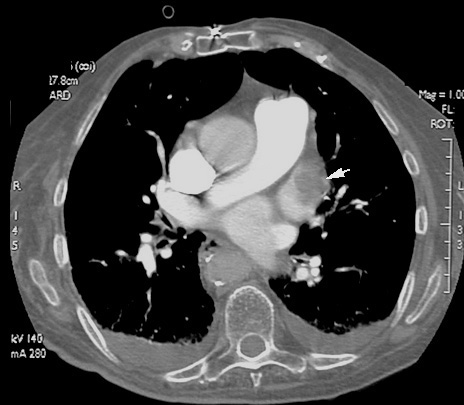

Clot in Left Atrium

A source for systemic embolism in this case.